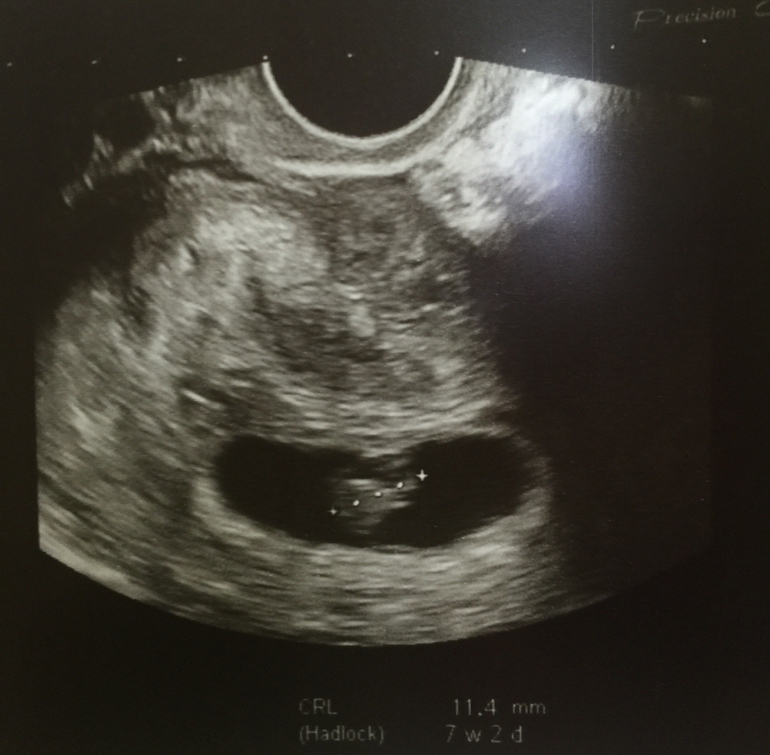

У нас получилось! Я беременна!Девочки, сегодня 56 дц и ровно 8 недель по месячным и я впервые услышала сердечко НАШЕГО РЕБЕНОЧКА .

Вот оно наше маленькое, но такое большое счастье